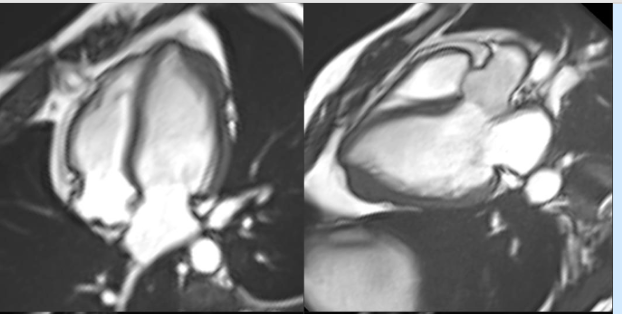

Not all hypetrophy is same!